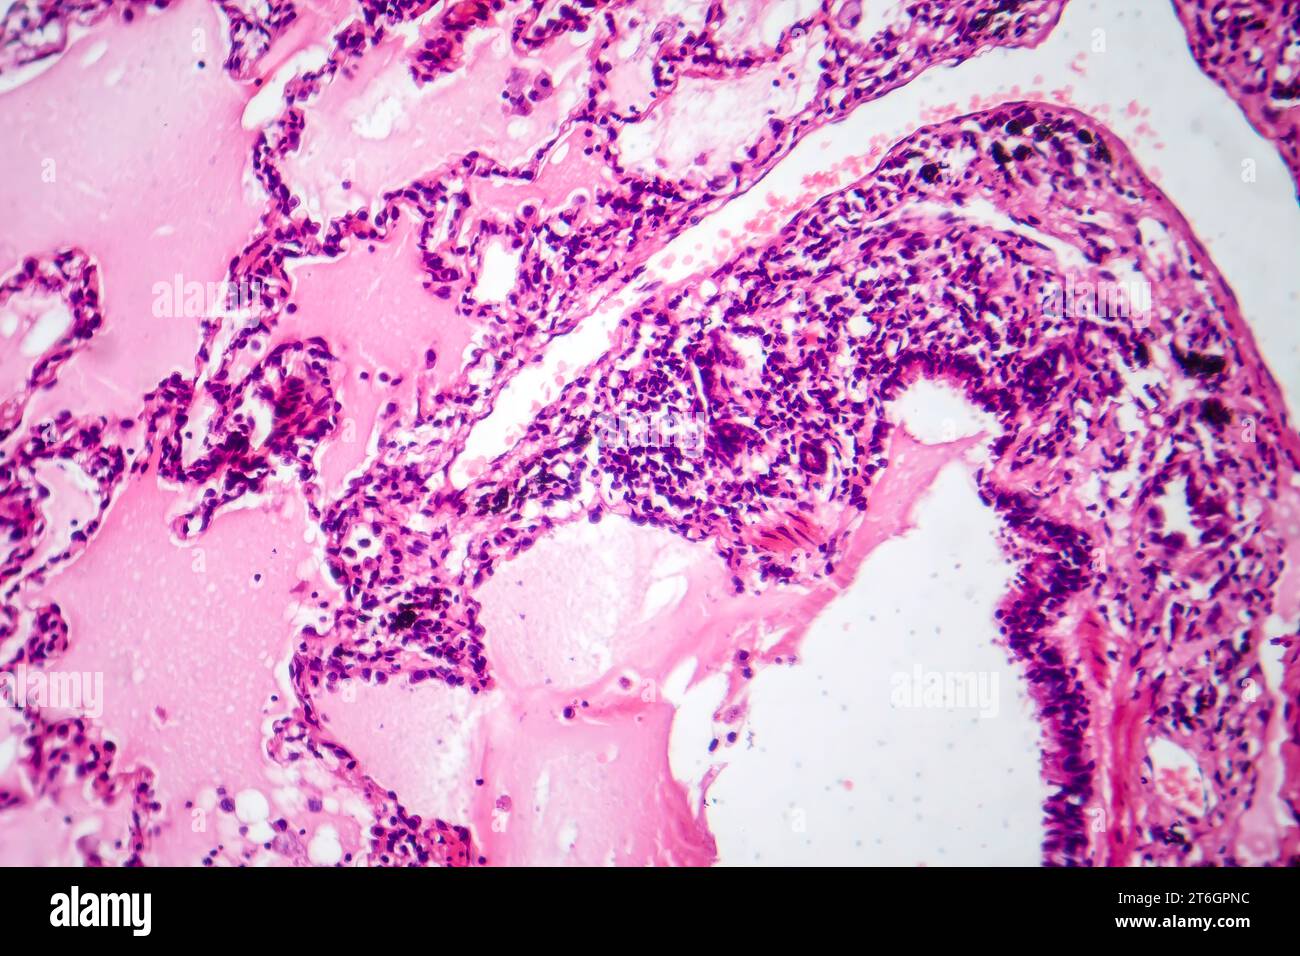

Human glandular cancer, light micrograph Stock Image C050/8381 Are Glandular Cells Cancerous This result means glandular cells that look different. — glandular cells are another type of cell found in the cervix. — it is covered with glandular cells. The exocervix (or ectocervix) is the outer part of the cervix that can be seen. — the risk that atypical glandular cell (agc) abnormalities reflect precancerous changes is as high. Are Glandular Cells Cancerous.

Photomicrograph of lung adenocarcinoma, displaying malignant glandular Are Glandular Cells Cancerous two types of cells line the surface of the cervix, and both can become cancerous. — the risk that atypical glandular cell (agc) abnormalities reflect precancerous changes is as high as 35. The exocervix (or ectocervix) is the outer part of the cervix that can be seen. This is the most common type of cervical. This result means. Are Glandular Cells Cancerous.

Photomicrograph of lung adenocarcinoma, displaying malignant glandular Are Glandular Cells Cancerous — atypical glandular cells: This result means glandular cells that look different. This is the most common type of cervical. When the glandular cells do not look normal, but they have concerning features that could. — the risk that atypical glandular cell (agc) abnormalities reflect precancerous changes is as high as 35. — adenocarcinoma is a type. Are Glandular Cells Cancerous.